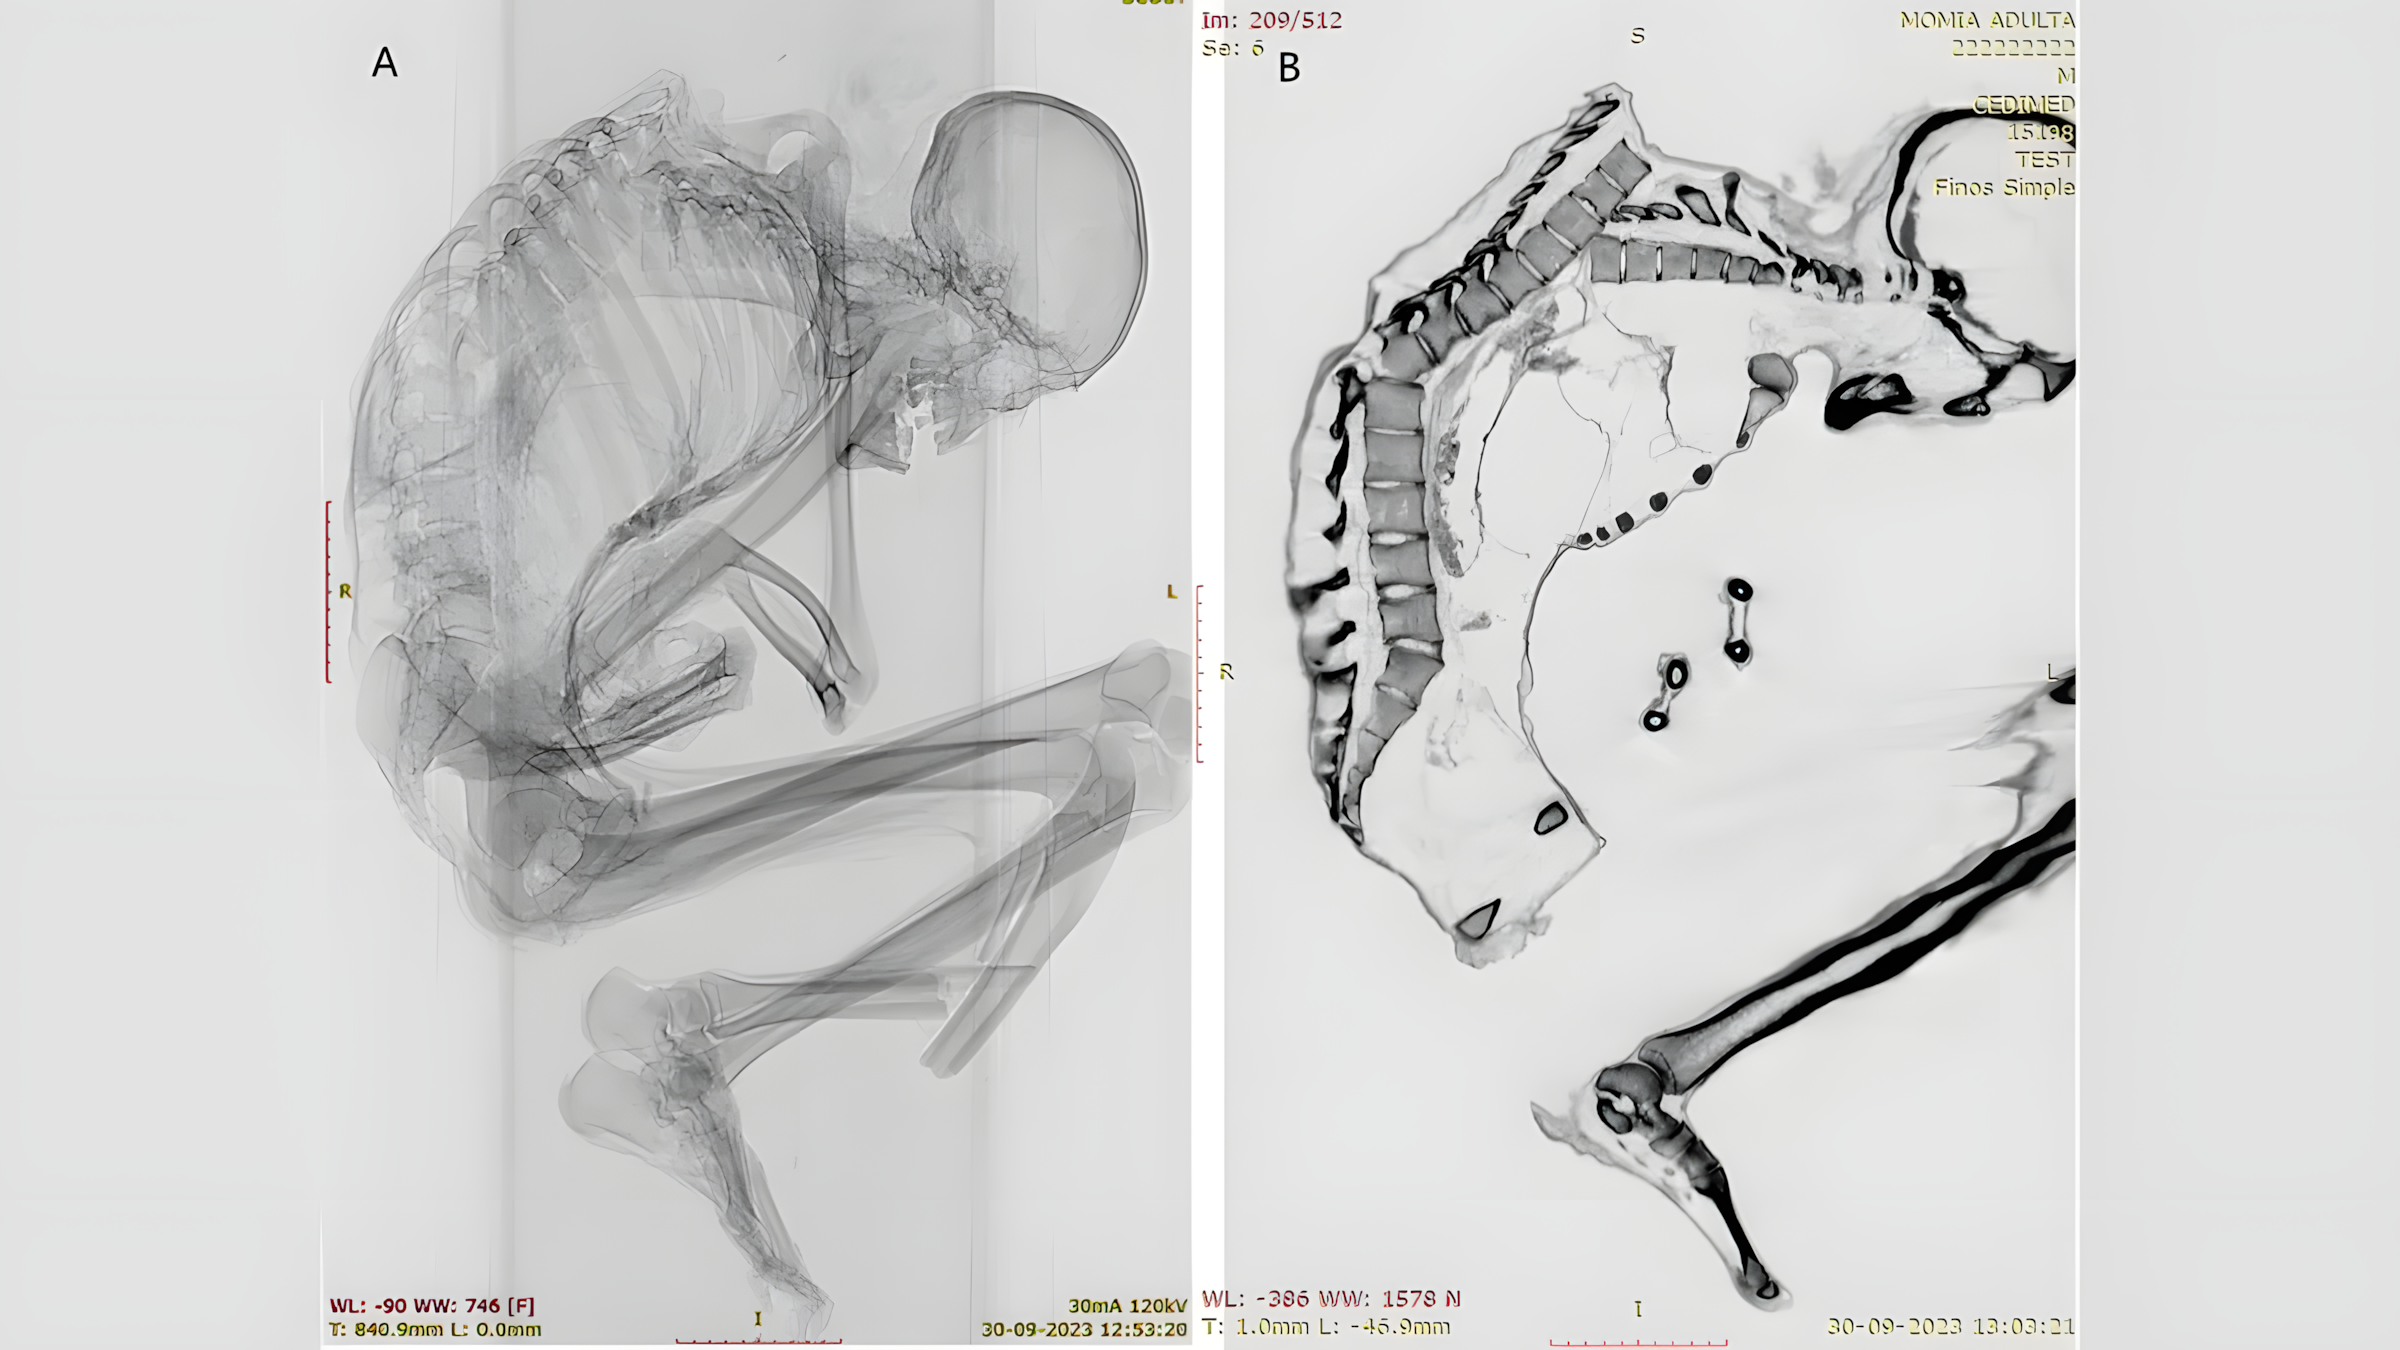

12월 15일 국제 골고고학 저널(International Journal of Osteoarchaeology)에 발표된 연구에서 칠레 산티아고 국립 자연사 박물관 고고학자 카탈리나 모랄레스Catalina Morales와 프란시스코 가리도Francisco Garrido는 CT 스캔과 X선 촬영을 통해 남성 사망 원인이 되었을 것으로 추정되는 광범위한 외상의 세부적인 모습을 밝혀냈다.

남성의 척추 윗부분에는 아물지 않은 골절이 여러 군데 발견되었다.

갈비뼈, 견갑골, 쇄골 골절도 있었는데, 이는 상부 등 부위에 "넓은 영역에 걸쳐 둔탁한 충격"이 있었음을 시사하며, "특히 왼쪽 흉곽 윗부분이 가장 큰 충격을 받았음을 보여준다"고 모랄레스와 가리도는 연구 논문에서 밝혔다.

이 충격으로 척추뼈 여러 개가 어긋나고 흉곽이 무너졌다.

또한 연구진은 척추 기저부 근처의 척추뼈에도 골절이 있음을 확인했는데, 이는 초기 상부 등 부상의 결과일 가능성이 높다.

상부 및 하부 척추 손상은 모두 "일반적으로 심각한 척수 손상 및 높은 사망률과 관련이 있다"고 연구진은 덧붙였다.

하지만 남성의 두개골, 목, 팔에는 부상이 발견되지 않았는데, 이는 남성이 머리를 숙인 자세로 충격을 받았음을 시사한다.